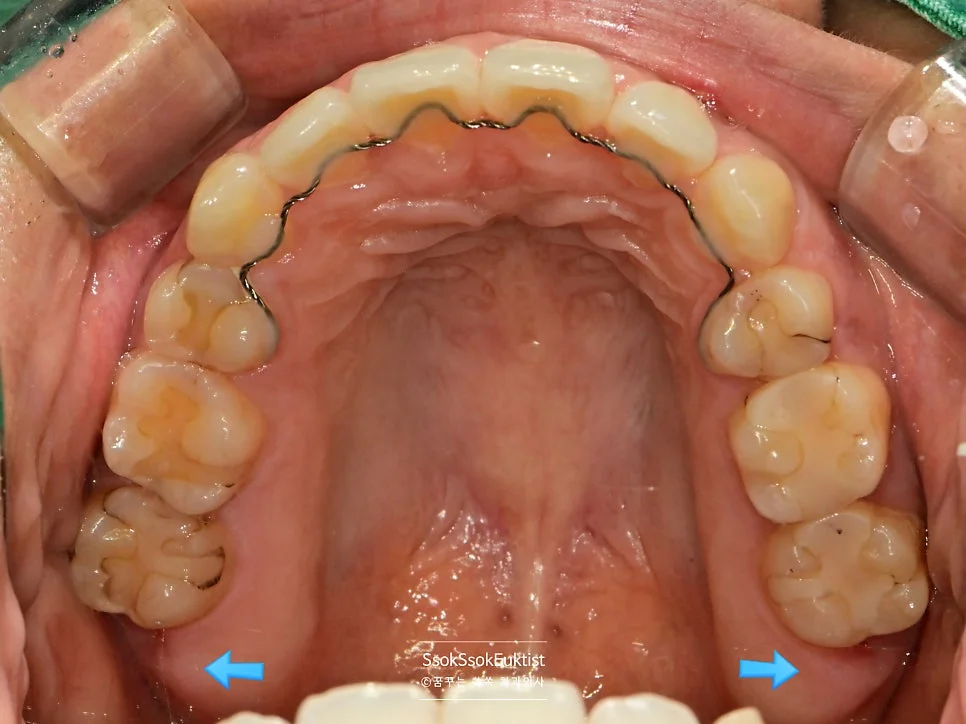

구강 전체 사랑니 4개 진단 사진

구강 정면 사진 — 사랑니 4개가 모두 존재하는 상태

사랑니는 4개가 다 있고, 다 발치해야 하는 상황이네요^^

파란 화살표로 표시되어 있는 치아가 사랑니입니다! 위 사랑니는 크기가 좀 작지만 비교적 얌전히 나있는데요!

아래 두 개의 사랑니를 보면 머리부터 충치가 상당히 진행되어 있는 것을 볼 수 있습니다. 아래 사랑니는 매복 사랑니이기 때문에 발치를 해야 하고, 위 사랑니는 아래 사랑니를 제거하면 닿는 치아가 없어 필요 없고 관리만 안 되는 사랑니이기에 발치를 하는 것을 추천합니다!^^